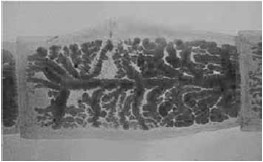

A fotomicroscopia ilustra uma proglote de Taenia solium.

As proglotes são estruturas corpóreas que participam do ciclo biológico do verme ao